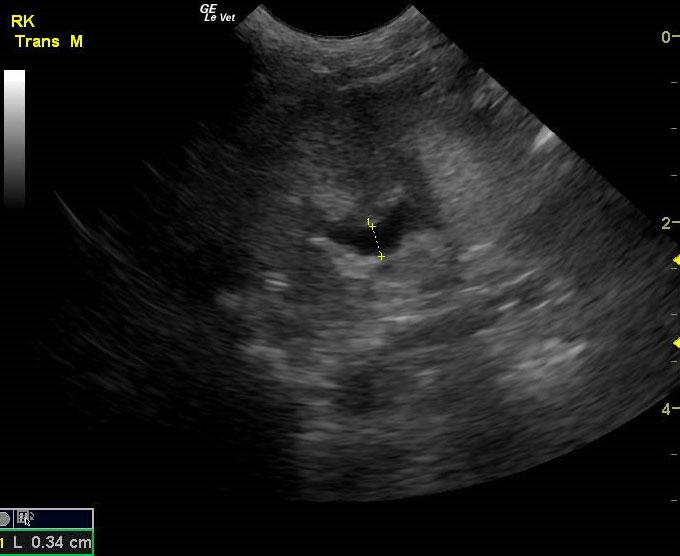

A 14-year-old neutered male Pomeranian dog was presented for evaluation of pollakiuria, diarrhea, inappetence, and lethargy. Abnormalities on physical examination included a painful, enlarged and symmetrical prostate, a very large and firm urinary bladder that could be expressed, and a grade III/VI heart murmur. On survey thoracic radiographs, calcification of the prostate gland was evident.